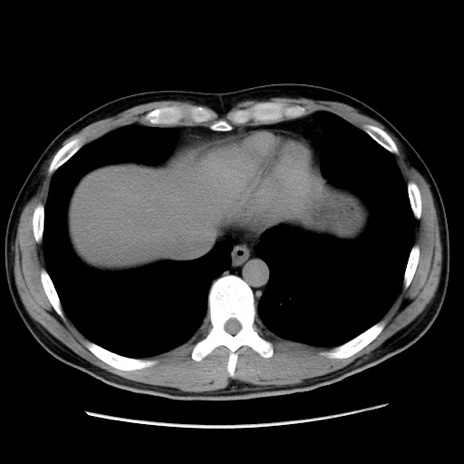

冠状断像

【症例】20歳代 男性

【主訴】心窩部痛

【現病歴】今朝より上腹部痛あり。一旦軽快していたが再度出現したため救急要請。昨日夕に白身の魚を含む刺身を食べた。

【身体所見】BP 136/89mmHg、HR 74/min、BT 37.0℃、腹部:膨満、軟、心窩部に圧痛あり。反跳痛なし、筋性防御なし、腸雑音やや亢進あり。

【データ】WBC 17700、CRP 0.48